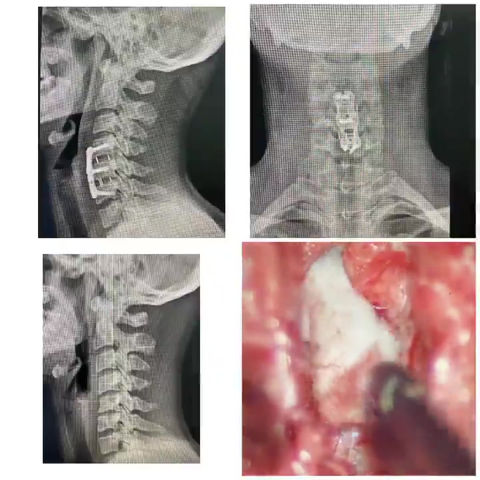

Complex Reconstruction of Cervical Spine by severe Myelopathy

47 years old patient Ms.Glenda falld down by walking in the street in February 2020. At the location of the accident was the patient paralyzed and couldn’t move her arms and legs for minutes. Ms. Glenda came to Dr. Basil 1 week later for a third opinion. Dr. Basil was the first surgeon , who diagnosed an OPLL ( ossified posterior longitudinal ligament ) C4/5 and C5/6 ( see video) with absolute bony stenosis of the spinal canal C4-C6 and severe Myelopathy/ Contusio spinalis ( injury to the spinal cord due to severe compression that may result from trauma, congenital stenosis, degenerative disease or disc herniation.)

The Patient had preoperitavely severe Ataxia ( unsteady gait ) , Paralyzed in her Right Arm and had numbness in the upper and lower limbs and couldn’t walk without support.

Dr. Basil performed a very complicated and critical surgery by the patient and removed microscopic tow vertebras C4 and C5 to decompress the spinal cord after adhesiolysis the Bone from the Thecal sack. Then he reconstruct the spinal Alignment with vertebral body replacement C4 and C5 with Platte and screws from the front ( anterior) and 4 days later from the back ( posterior) screws fixation C3-C6 for the maximal stability. Both surgeries done without complications.

The patient could mobilized after the first surgery and her gait improved very well. Now 3 months post surgery Ms. Glenda recovered completely, no weakness more, no numbness and can walk properly without any support and she works again.